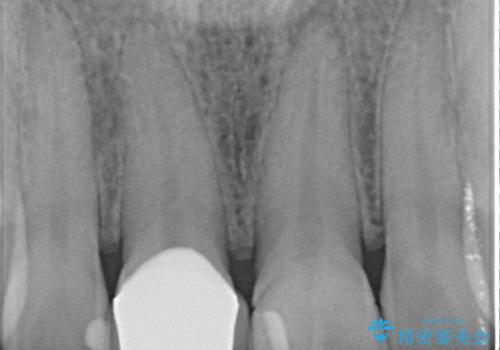

- 右上の前歯が折れたことを主訴に来院された患者様です。

歯が折れた部分は他院により応急処置で仮止めされていました。

欠けた範囲が大きかったため、セラミッククラウンによる補綴治療を行いました。

※左上の前歯(外国で治療されたとのこと)の失活が疑われたためそちらの治療も提案しましたが、ご希望されませんでした。